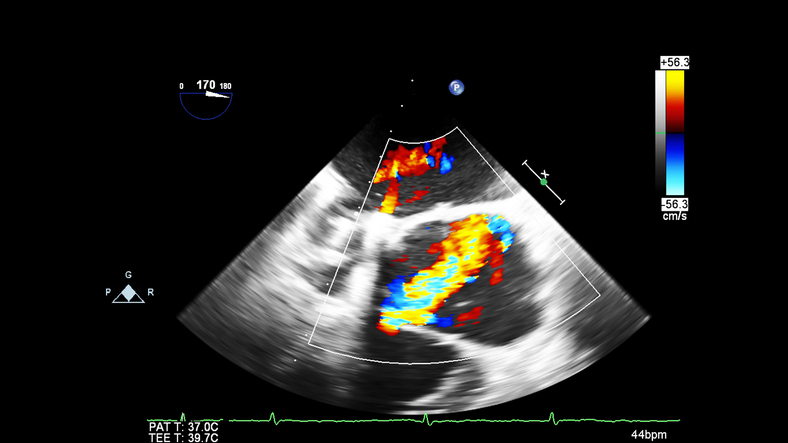

Point-of-care transesophageal echocardiography (TEE) is becoming more widely used in cardiac arrest. It has four main advantages over TTE: a reliable sonographic window, continuous imaging of the heart during resuscitation, elimination of pauses in chest compressions, and potential to detect abnormalities that are more difficult to visualize on TTE. [15] However, barriers exist to widespread implementation of TEE in the ED, namely access to training, the cost of purchasing, storing, and reprocessing equipment. More research highlighting the benefits of point-of-care TEE is needed, and access to equipment and training opportunities would be greatly beneficial to the emergency medicine community.